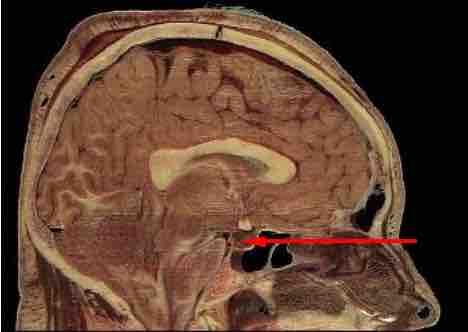

Pituitary location

The location of pituitary gland in the human brain.

This illustration shows where the pituitary gland is located in the brain. It protrudes off the bottom of the hypothalamus at the base of the brain, and rests in a small, bony cavity.

The pituitary gland

In this image, the pituitary gland is referred to by its other name, the hypophysis.